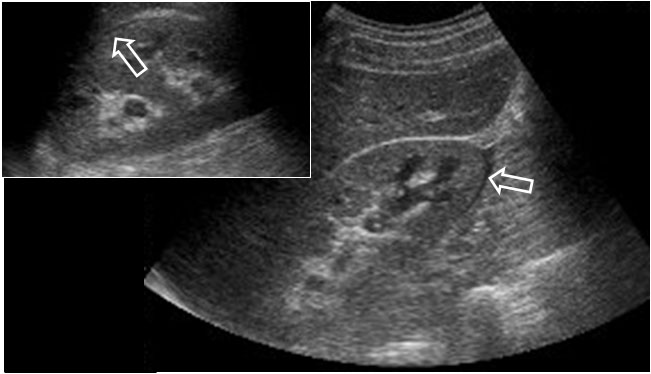

SIGNO DEL OJO DE LA CERRADURA

La identificación de hidronefrosis por ecografía en un feto varón o en un recién nacido obliga a descartar que la causa sea la presencia de válvulas de uretra posterior. Ésta se reconoce por el engrosamiento de la pared de la vejiga y por la dilatación de la uretra posterior. El ojo de la cerradura se refiere a la imagen de la vejiga (que forma la parte superior redondeada) y la uretra posterior dilatada (la parte inferior de la cerradura). Se entiende mejor viendo un ejemplo: http://radiopaedia.org/articles/keyhole-sign.